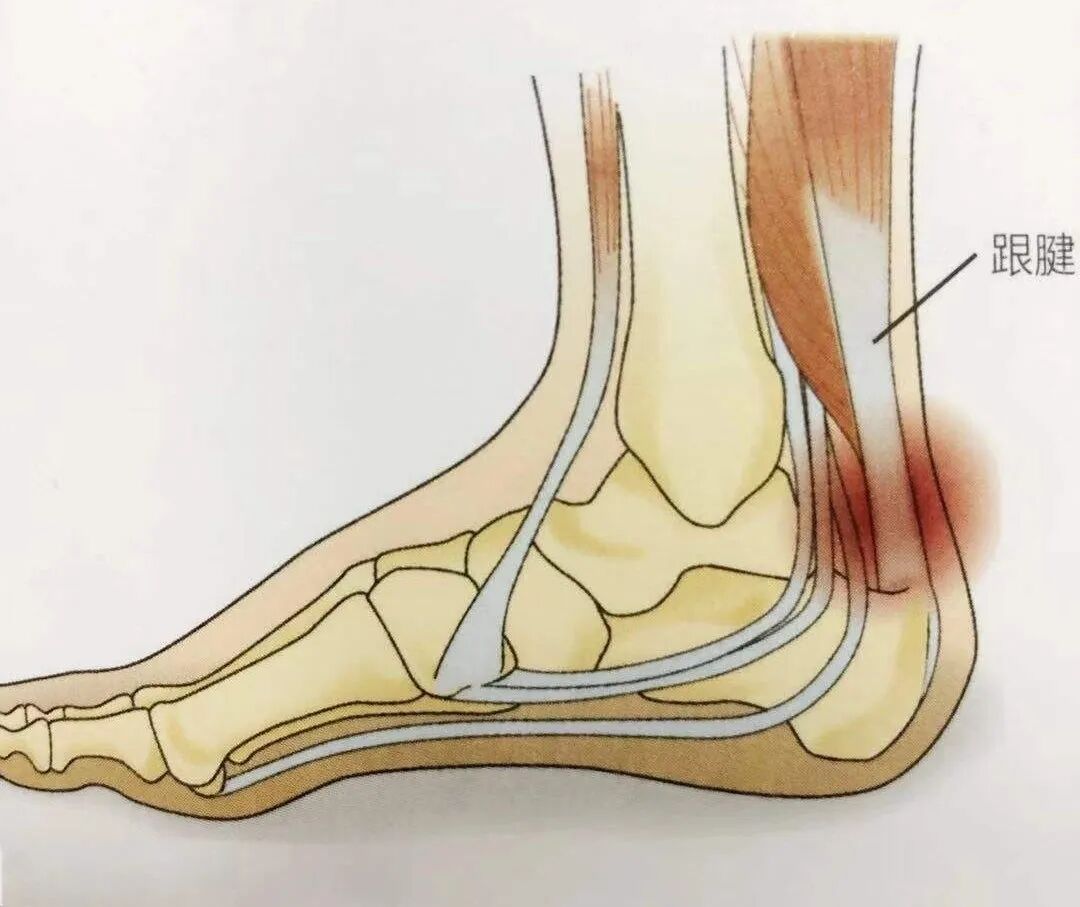

跟腱炎

跟腱炎主要是指跟腱及周围的腱膜在行走、跑跳等剧烈运动时遭受劳损,发生部分纤维撕裂、充血、水肿、变性,甚至钙化等,以局部疼痛,足跟不能着地,踝关节背伸疼痛加重等为主要表现的无菌炎症性疾病。ESWT治疗跟腱炎有效率为 70%~95%。